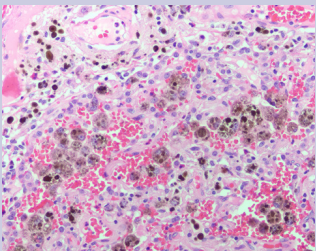

Pathology sections from the left lingula resection revealed prominent areas of hemosiderin deposition both within alveolar macrophages and within the interstitium [Figure 5], especially hemorrhage with no evidence of vasculitis or capillaritis.

Figure 5: Significant hemosiderin deposition within alveolar macrophages and the interstitium (200x). Hemosiderin deposition would not be expected if these collections of blood were an artifact of the surgical resection. There is no evidence of vasculitis or capillaritis

The most prominent hemosiderin deposition was seen in a portion of lung that contained an abnormal collection of small arteries and veins with associated fibrosis that forms a vascular tangle. This vascular tangle was located at the periphery of the lung near the pleural surface and surrounds a broncho-vascular structure that displays traction bronchiectasis [Figure 4 & 6].